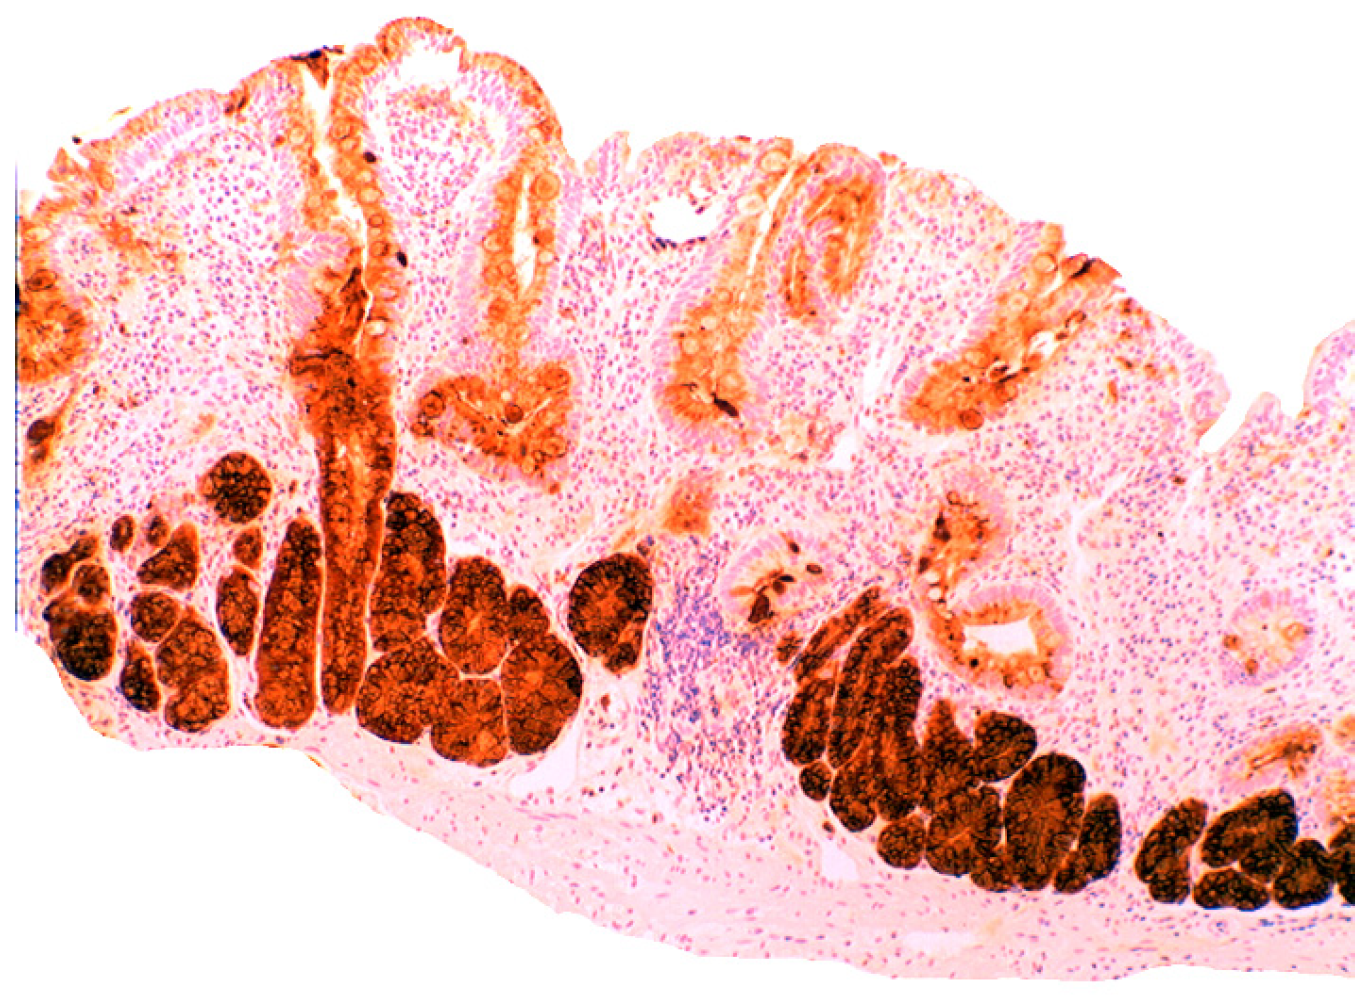

In active ulcerative colitis, lysozyme is up-regulated in metaplastic Paneth cells (left colon) and in the deep half of the crypts (Figure 14). In ulcerative colitis in remission, lysozyme is up-regulated in metaplastic Paneth cells [9] (left colon, Figure 15). No lysozyme expression is recorded in the crypts. In Crohn’s colitis lysozyme up-regulation is found in metaplastic Paneth cells (left colon), in the crypts as well as in the lamin propria mucosae [9] (Figure 16). The increased lysozyme production in the colonic mucosa in patients with inflammatory bowel disease may highlight an amplified mucosal protection against the pathogenic bacteria proliferating in the colonic microenvironment in these patients [70,71,72,73,74,75,76,77,78,79,80,81].

Figure 15. Ulcerative colitis (in remission). Marked lysozyme immunoreactivity in hyperplastic- metaplastic Paneth cells in the bottom of the crypts of the left colon, (lysozyme immunostain, ×10).